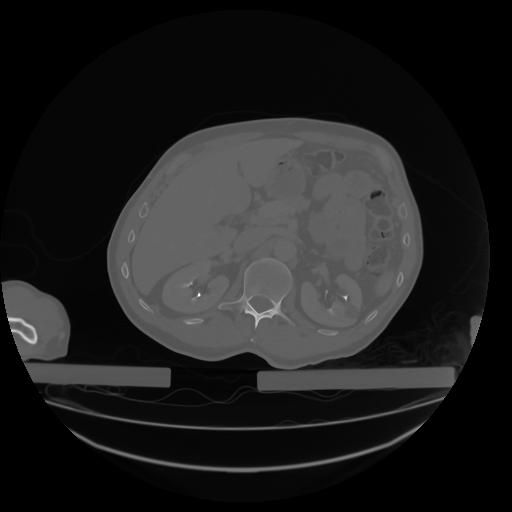

27 CUERPO,CE,Axial,3.0,CUERPO,,